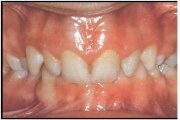

Ruumipuudus eesmiste hammaste osas